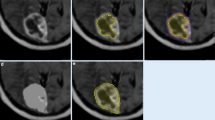

In this retrospective study, patients with BMs scanned with MRI between January 1, 2018, and December 31, 2021, were screened. Inclusion criteria were: (1) at least one sub-centimeter BM with an integer millimeter-longest diameter was noted in the MRI report; (2) patients were a minimum of 18 years of age; (3) patients with available pre-treatment three-dimensional T1-weighted spoiled gradient-echo MRI scan. The screening was terminated when there were 20 lesions in each group. Lesion volumes were measured with the help of intelligent automation software Jazz (AI Medical, Zollikon, Switzerland) by two readers. The Kruskal-Wallis test was used to compare volumetric differences.